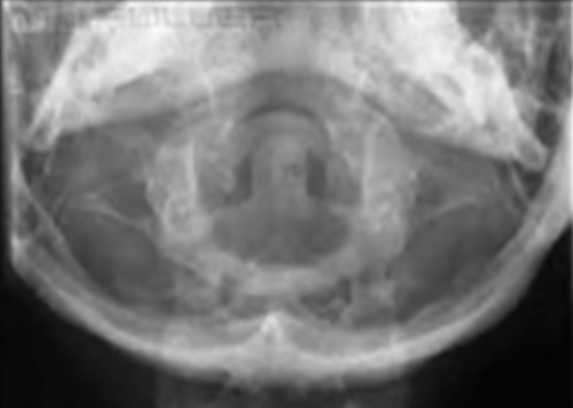

what view is this

ap dens, fuchs

how is the dens visualized using fuchs method

dens visualized within the opening of the foramen magnum surrounded by the ring of C1